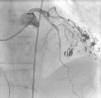

Case reportA 81-year-old Caucasian man, with a history of esophageal squamous cell carcinoma diagnosed 9 months earlier treated by total esophagectomy (stage pT3, N0, Mx, R0), was admitted to our institution due to acute stroke. He had no known previous cardiovascular risk factors. The day after admission, he complained of chest discomfort and an electrocardiogram (ECG) was performed, revealing ST-segment elevation in leads V2–V4. Due to the suspicion of acute myocardial infarction (AMI), a coronary angiogram was carried out. No significant coronary artery lesions were found (Figure 1).